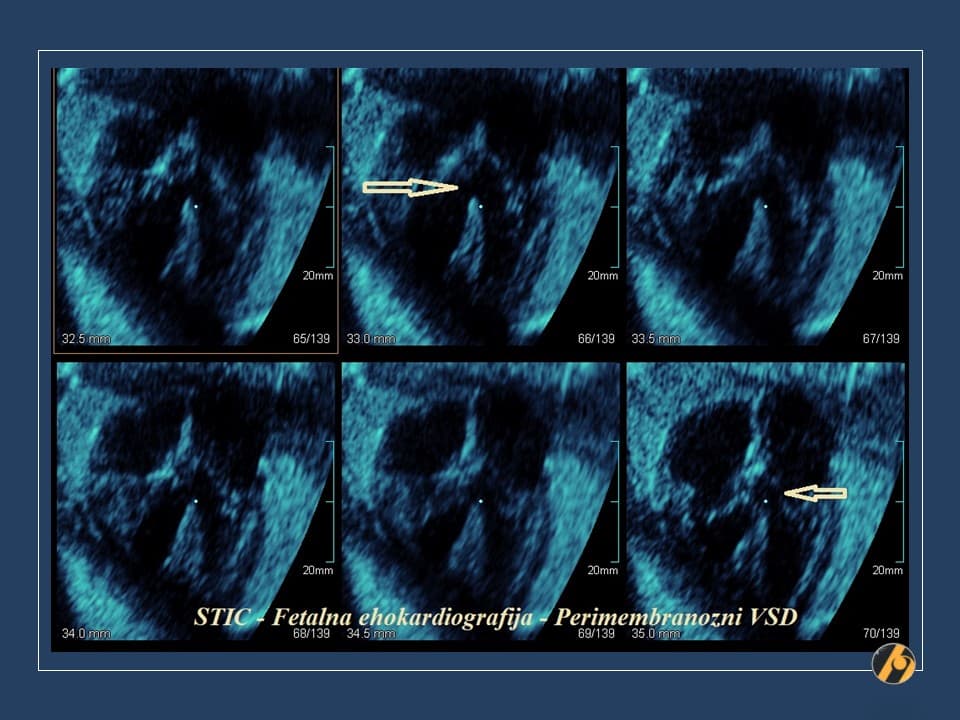

Oko 20. tjedna trudnoće obično se obavlja detaljan ultrazvučni pregled drugog tromjesečja, poznat kao morfološki ultrazvuk ili anomaly scan. Tijekom tog pregleda procjenjuju se razvoj i anatomija fetusa, razvoj mozga, srca i drugih organa, količina plodove vode te položaj i izgled posteljice.

Ovaj pregled omogućuje liječniku da procijeni razvija li se beba uredno te pruža važan uvid u tijek trudnoće, kao i da preporuči dodatne pretrage kao što su fetalna neurosonografija ili fetalna ehokardiografija.